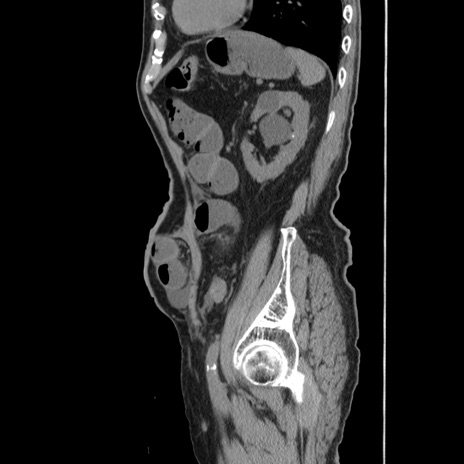

症例24(矢状断像)

【症例】80歳代男性

【主訴】左側腹部痛、嘔吐

【現病歴】本日早朝より左腹部に痛みあり。昼頃嘔吐認めたため、救急要請。

【既往歴】直腸癌(Mile手術)、胆摘

【身体所見】意識清明、BT 35.9℃、BP 221/93mmHg、SpO2 97%(RA) 、腹部:左ストーマ周囲に限局性の腹部膨隆あり。 膨隆部自発痛・圧痛あり・軟。

【データ】WBC 7700、CRP 0.09